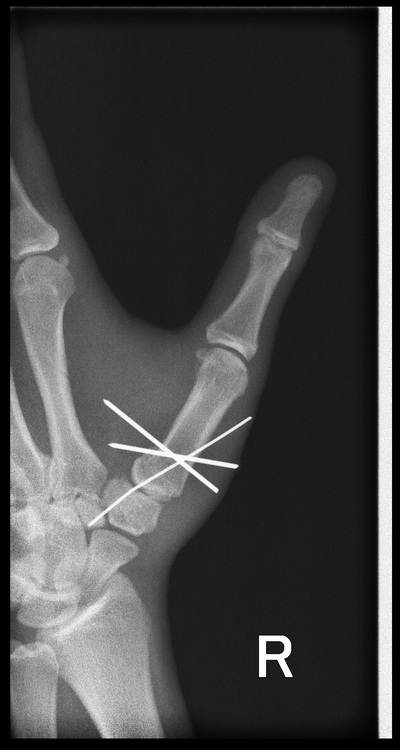

Утро травматолога

за 15 минут до конца дежурства:(

играл в футбол и упал на отведенную руку

нет одну. два снимка